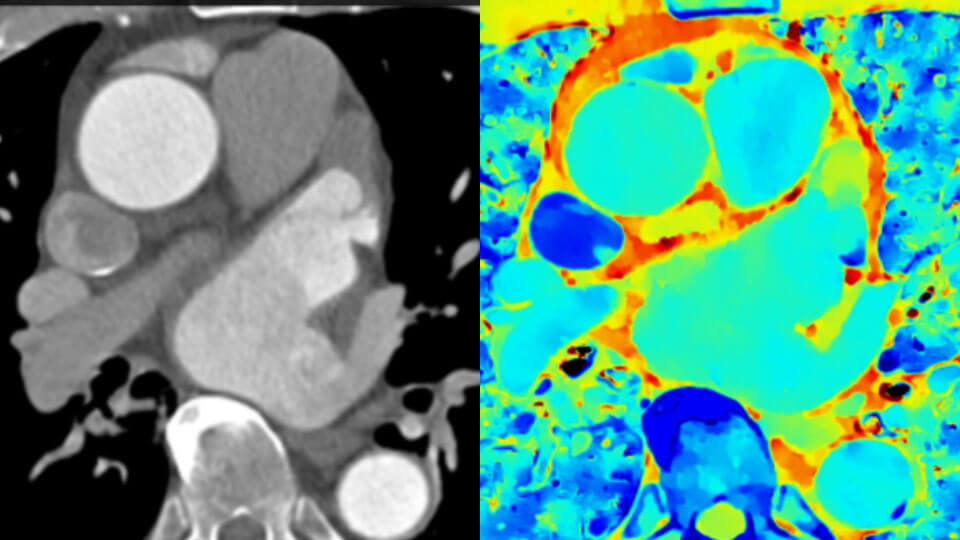

Conventional CT image (left) Spectral-detector CT image (right)

Now you can easily have both the “where things are” of conventional CT combined with the “what things are” revealed by spectral-detector data. Layers of rich spectral data improve tissue characterization and visualization, and may reduce the need for follow-up scanning for sub-optimal exams and incidental findings.